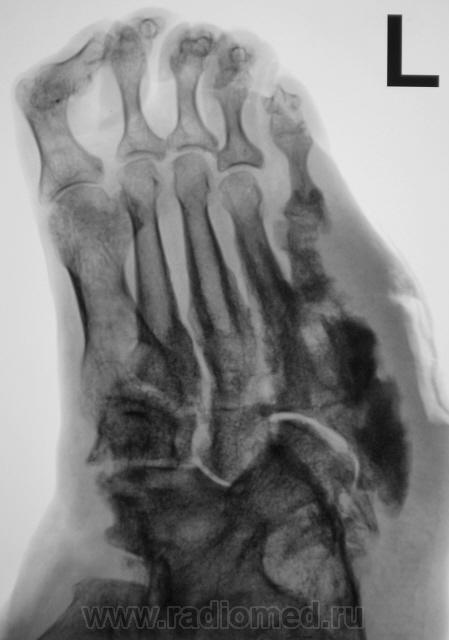

Пациентка направлена на рентгенографию стоп.

Левая стопа.

Направительный диагноз - "Диабетическая ангиопатия".

По правой стопе я бы тоже поставил Гарре, но слева такое вылезает. Может все-таки системное?

Хирург, увидев только одну стопу - правую, левая, еще была в работе, ответственно заявил - "остеогенная саркома"...

Системное поражение, возможно как следствие диабетической ангиопатии;слева V плюсневая кость с прерывистым контуром ( возможно остеонекроз на фоне ангиопатии). Не видел подобного ранее.

Картинка вобрала в себя все, что клинически называют "диабетическая стопа". Здесь последствия и ангиопатии, и нейропатии, и присоединившейся инфекции. По-моему, имеется и трофическая язва. Прямо студенческий случай. Хотя, я тоже ранее таких стоп не видел.